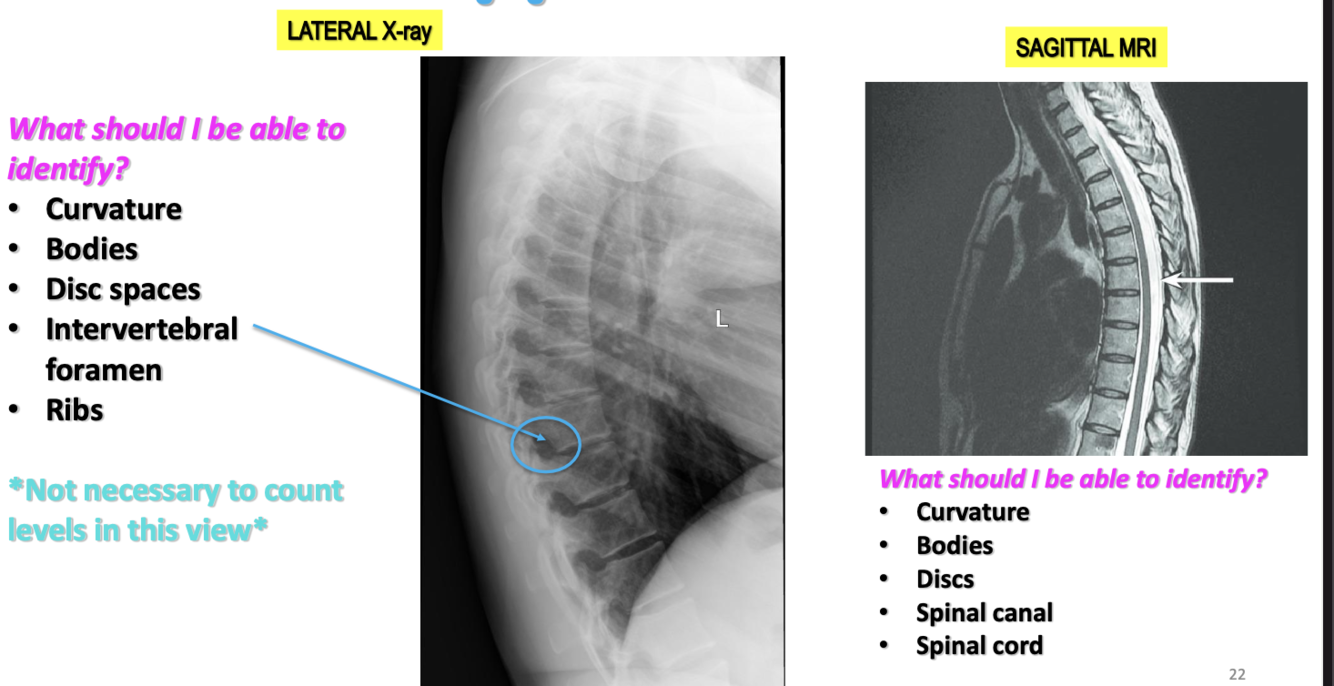

Imaging of Thoracic Vertebrae Contd

19